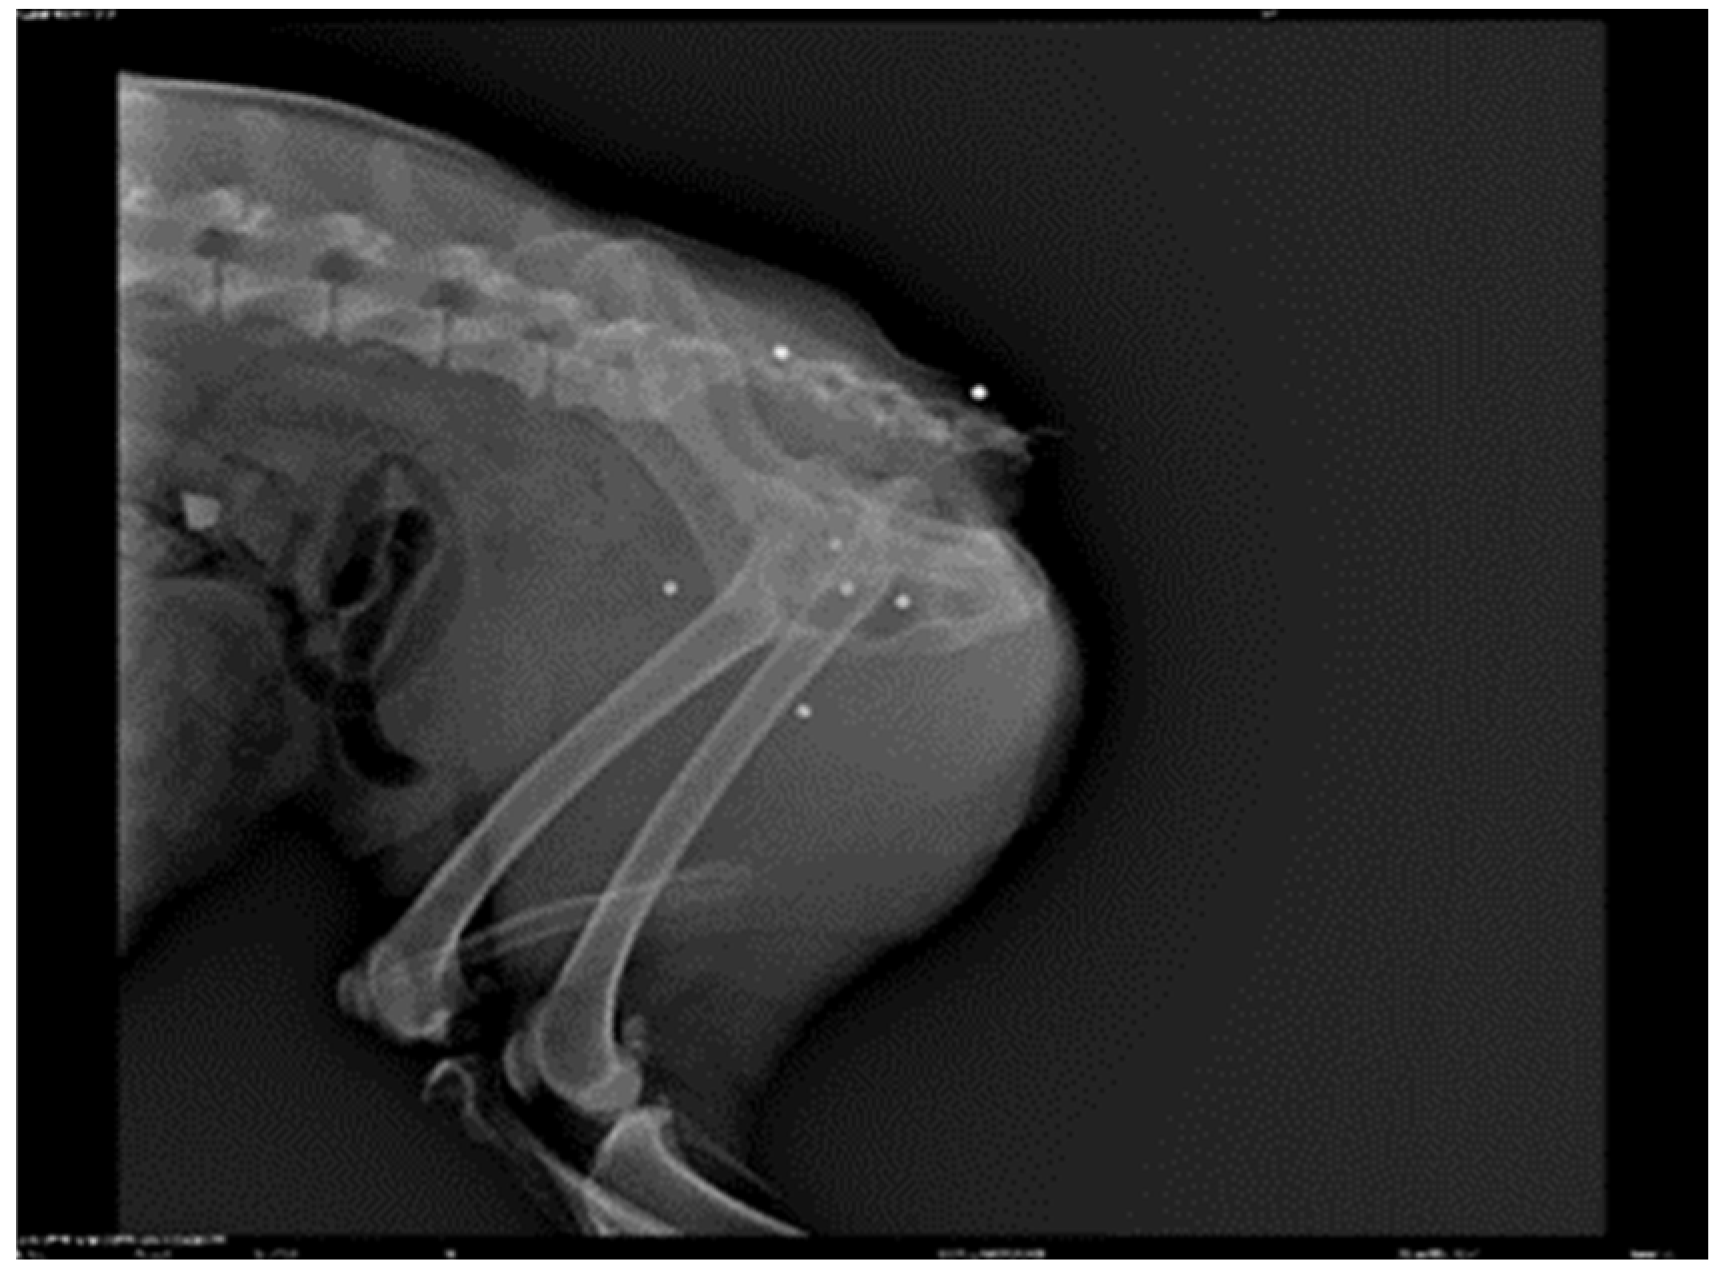

2.1. Patient Details a 7-Year-Old Male Canine Setter, 23 kg Was the Subject of This Study

2.3. Assessment

3. Results